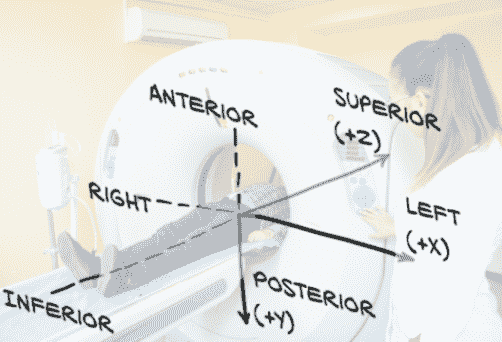

正如我们之前提到的,处理 CT 扫描时,我们将数组维度称为索引、行和列,因为 X、Y 和 Z 有不同的含义,如图 10.6 所示。病人坐标系定义正 X 为病人左侧(左),正 Y 为病人后方(后方),正 Z 为朝向病人头部(上部)。左后上有时会缩写为LPS。

图 10.6 我们穿着不当的病人展示了病人坐标系的轴线